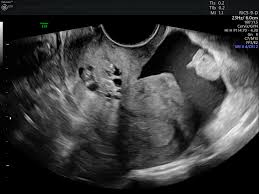

Okay, let’s break down the cul-de-sac in ultrasounds. It’s a term you’ll hear if you’re having a pelvic ultrasound. It’s basically a pouch, or a little pocket, in the pelvic cavity.

You see, women have two of these cul-de-sacs. One’s in the front of the uterus, between the uterus and the bladder. This is called the anterior cul-de-sac. The other cul-de-sac is behind the uterus, between the uterus and the rectum (your bottom). This one is called the posterior cul-de-sac.

These cul-de-sacs are important because they can hold fluid. During an ultrasound, your doctor might look for fluid in these cul-de-sacs. This could be a sign of several things, like:

The cul-de-sac is a common finding in ultrasounds. Your doctor will likely mention it, especially if they see fluid there. Don’t worry – it doesn’t necessarily mean anything is wrong. But it’s important to know what it is and why your doctor might be looking at it.